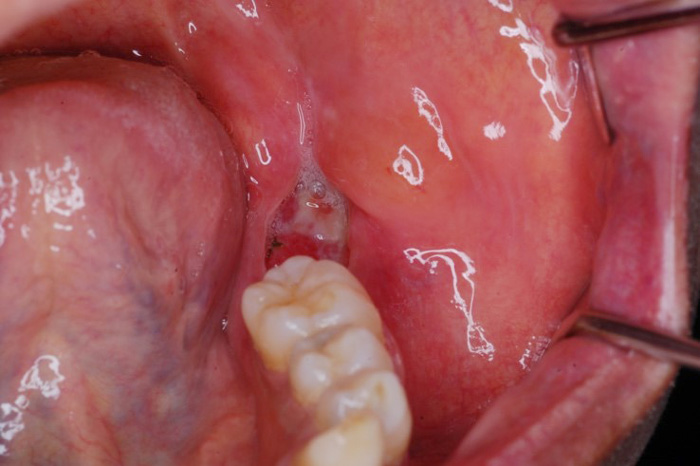

(注1)[智歯周囲炎]

智歯(おやしらず)は18歳頃から萌出を開始しますが、現代の日本人の顎の大きさは小さくなっている傾向にあります。第3大臼歯である智歯はスペースがないため顎骨に埋伏している状態(埋伏智歯または水平埋伏智歯)の患者様が多く見られます。

このような顎骨に埋伏した智歯が原因となり歯肉の腫れ、痛みを繰り返し起こすことがあります。

当科では、術前に歯科用3次元CTを用いて正確な診断を行い、炎症がある場合は抗生剤を用いて消炎後、抜歯を行っています。埋伏智歯の場合、歯肉粘膜の切開、骨の削除、智歯の分割、創部の縫合を必要とします。